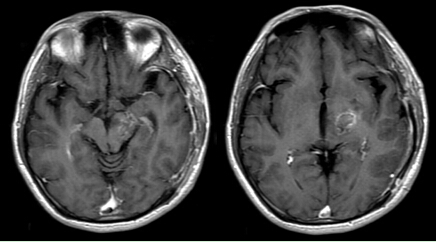

图1 术前MRI片